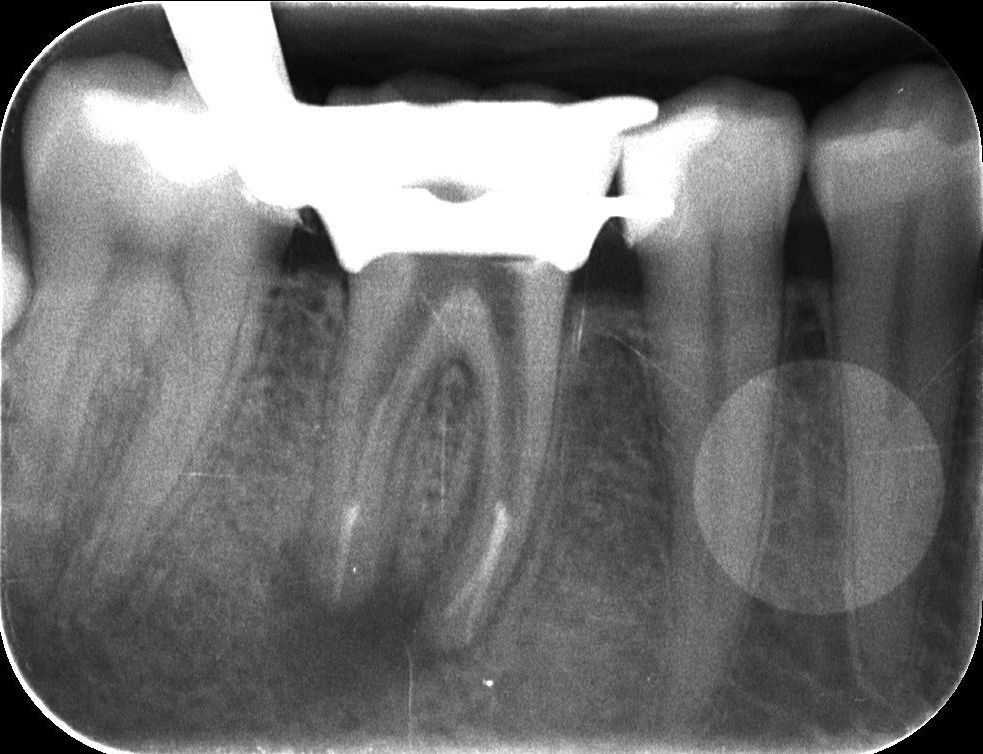

Dr. Kovács Kitti páciense egy három éve készült gyökértöméssel kapcsolatos panaszával kereste fel rendelőnket. A kérdéses fog az utóbbi időben bizonytalan panaszokat produkált. Néha kifejezetten fájt, néha a páciens „érezte”, hogy van foga, néha pedig teljesen panaszmentes volt. A vizsgálatot egy kis röntgenfelvétel készítésével kezdtük, majd ezt tüzetes szájüregi vizsgálat követte. A fog kopogtatásra érzékeny volt, illetve a röntgenfelvételen egyértelműen látható a csontban lévő krónikus gyulladás (amelyet az alsó képen pirossal rajzoltunk körbe), illetve az ezt kiváltó ok, a rövid gyökértömés (amelynek hiányzó szakaszát sárgával jelöltük).

mikroszkópos gyökérkezelés 1.kép